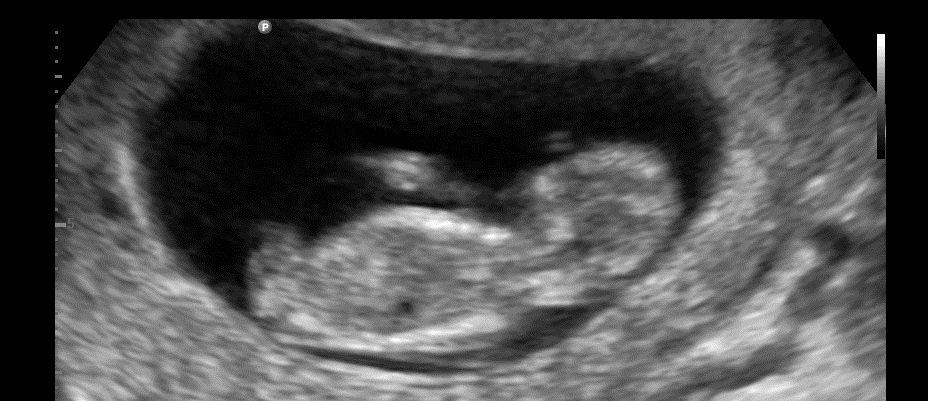

Any guesses please? :)

Any other pics? There is nothing showing gender here. Side profile?

I'm not sure that's the nub either but if it is poss boy:)

Maybe boy

Maybe boy?